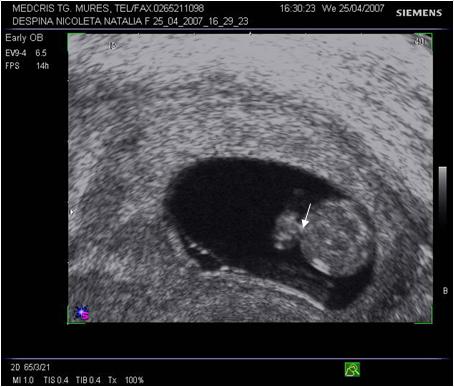

Fig. nr.123 Hernie fiziologica la 11 saptamani, fat in sectiune longitudinala.

( sageata)

Fig. nr.124 Hernia fiziologica fetala in sectiunea transversala abdominala.